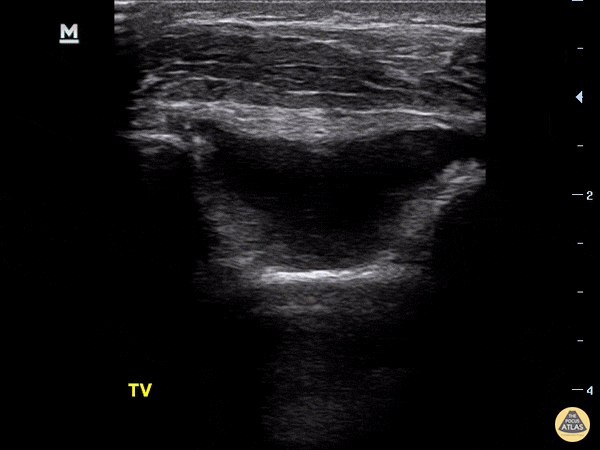

15 year old fell on left elbow, pain and swelling over left elbow on exam. Raised fat pad in the olecranon fossa of left humerus as compared to right humerus. A raised fat pad is suggestive of an elbow injury, more commonly a supracondylar fracture. Dr. Sathya Subramaniam - Kings County/SUNY Downstate - Pediatric EM Fellow